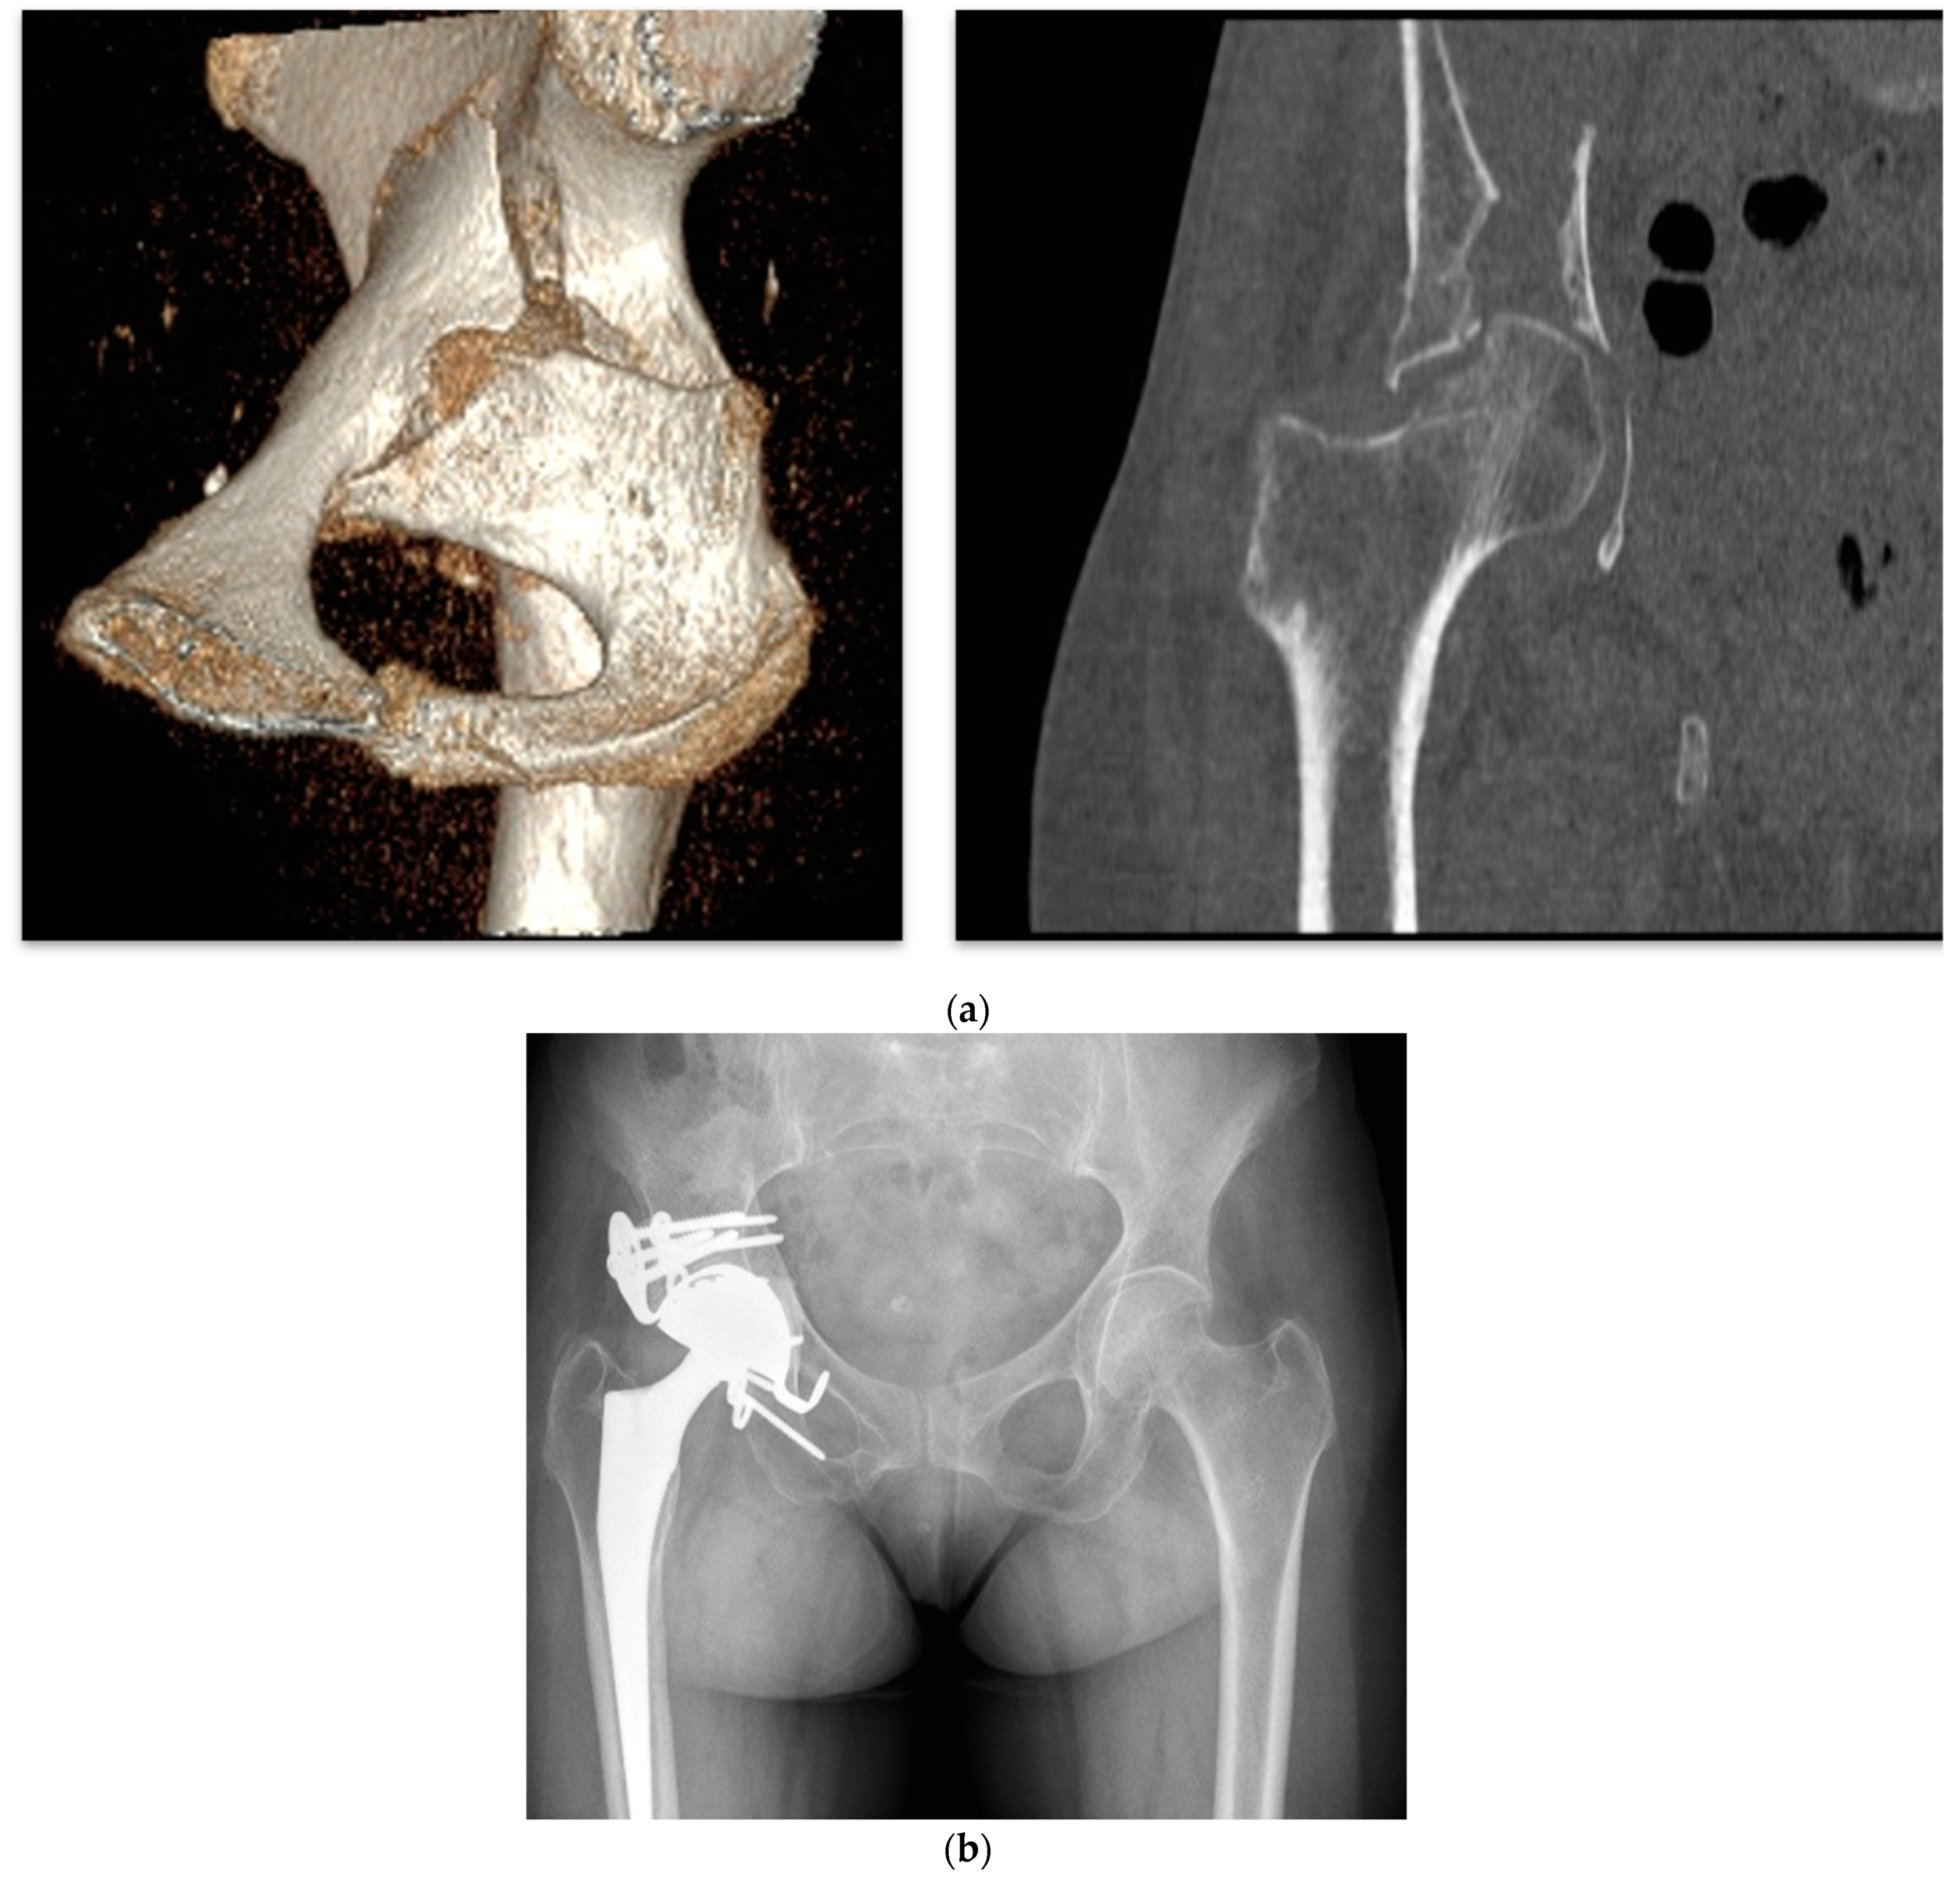

4.3. Acute THA in Acetabular Fractures